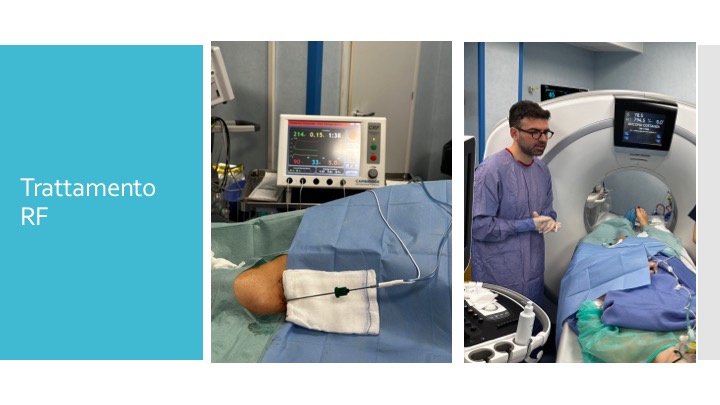

La termoablazione è una tecnica mini-invasiva guidata dai raggi X. Consiste nell’inserire un ago sottile nel nodulo osseo e, attraverso l’ago, viene erogata energia termica (calore) per “bruciare” le cellule tumorali.

- Guida per immagini: il radiologo utilizza raggi X (fluoroscopia o TAC) per guidare l’ago con precisione fino all’osteoma osteoide.

- Posizionamento dell’ago: l’ago viene inserito attraverso la pelle e posizionato esattamente al centro del nodulo osseo.

- Ablazione termica: attraverso l’ago viene erogata energia termica che distrugge le cellule tumorali.

- Fine della procedura: l’ago viene rimosso e viene applicato un bendaggio.

- Poco dolorosa: viene eseguita in anestesia locale o sedazione.